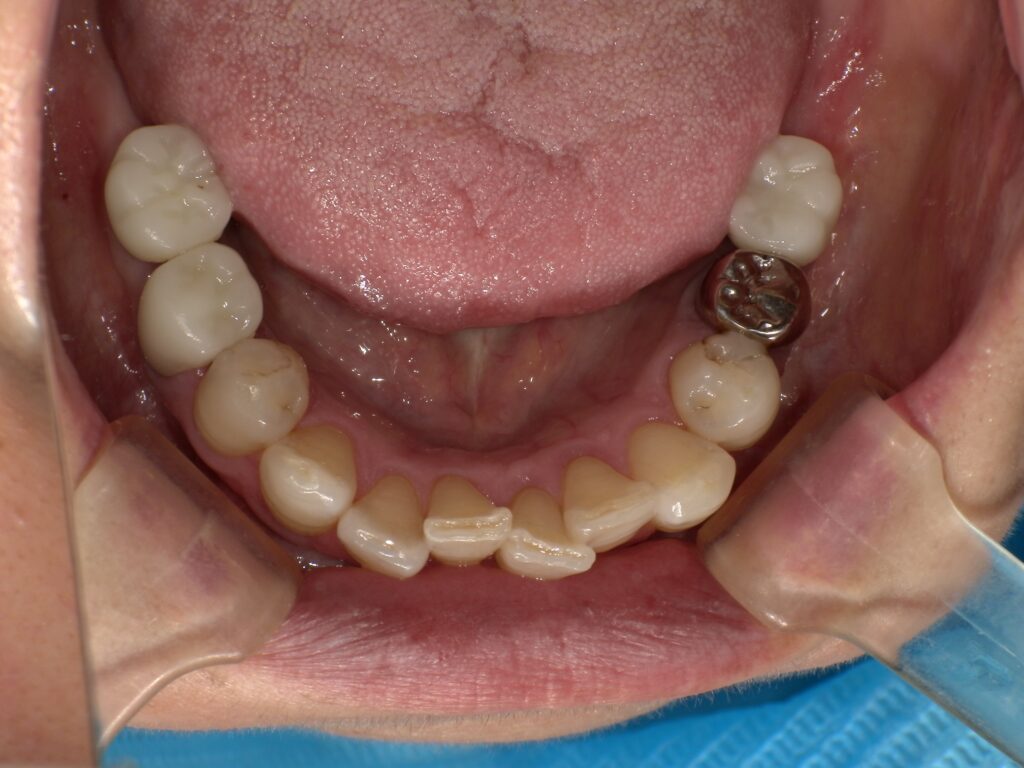

BEFORE

主訴

全体的に見た目を綺麗にしたい。奥歯でしっかり噛みたい。

診断名・主な症状

臼歯部欠損

年齢

70歳

治療内容

インプラント埋入(右上4・6,左上4・6,右下6,左下6)

ジルコニアBr(右上3―左上3)

ジルコニア(右下5,左下5)

治療期間/

通院回数

インプラント 1年5ヶ月/13回

ジルコニアBr、ジルコニアクラウン 3ヶ月/10回

費用

インプラント: 2,552,000円

その他治療: 640,000円

合計 3,192,000円

*いずれも税込